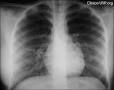

Indice cardiotoracico

Relación entre el diámetro del corazón y el del tórax, medida sobre una radiografía de frente. No debe sobrepasar de 0,50 en el adulto y de 0,55 en el lactante.